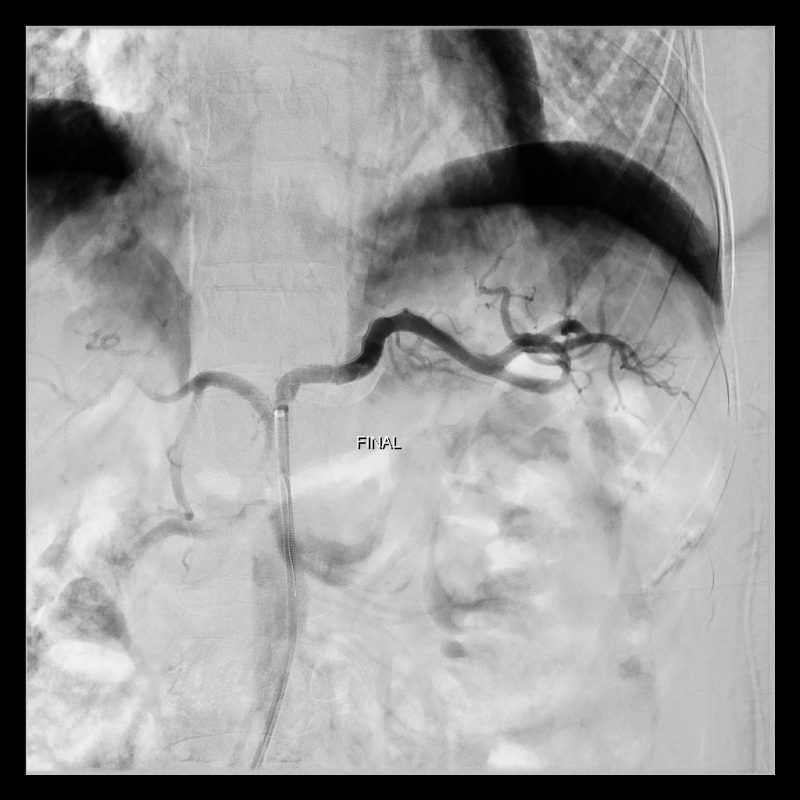

Tratamento de aneurisma da artéria Esplênica por implante de Stent revestido.

Aneurismas da artéria esplênica (artéria que nutre o baço) acomete mais mulheres multíparas (que tiveram muitas gestações). Neste vídeo demonstramos o tratamento dum aneurisma da artéria esplênica por via endovascular (através de cateterismo da artéria Femoral).